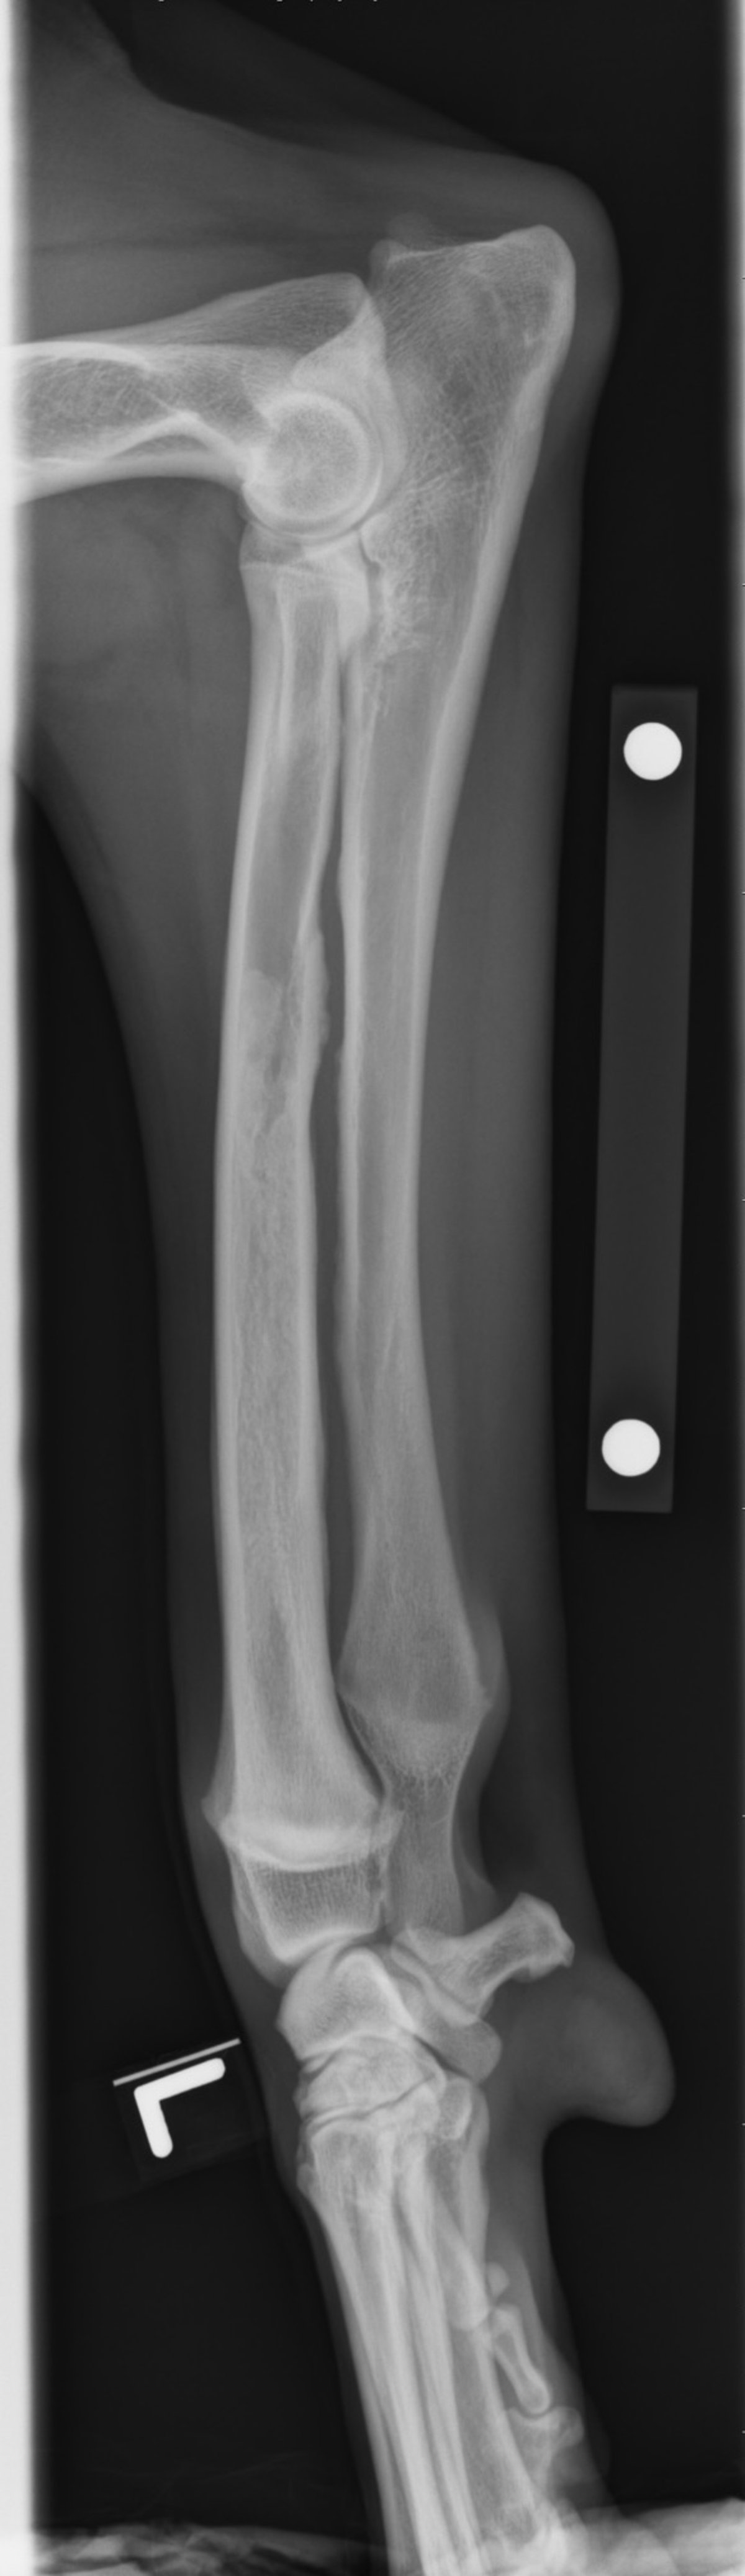

Angular Deformity of the Forelimb in Dogs and Cats

Angular limb deformity in dogs and cats is a condition characterized by abnormal spatial alignment of bones in a limb. This issue most commonly affects forelimbs, particularly the radius and ulna, and can arise because of asynchronous growth of paired bones, traumatic injury of the physis during development, or hereditary breed characteristics (eg, of Bulldogs, Pugs, Boston Terriers, Basset Hounds, Dachshunds).

The distal ulnar physis accounts for 80% of total ulnar growth and is the most common location for physeal injury. Asynchronous growth of the radius and ulna leads to shortened limbs, cranial bowing, torsion, and valgus or varus deformity of the radius and ulna, as well as to elbow joint or carpal joint subluxation.

Clinical signs of angular limb deformity include lameness and decreased, painful motion in the joints adjacent to the deformity, such as elbow or carpal joints for radius and ulna deformity.

Radiography reveals the bone deformations and premature closed physes. Nonfunctional physes can have a normal radiographic appearance; therefore, the presence of open physes does not rule out physeal damage (see ). CT scans provide additional information for complete evaluation of complex angular deformities.